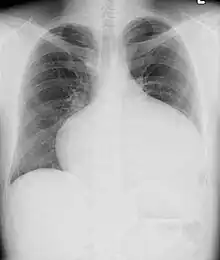

Adults with an uncorrected ASD present with symptoms of dyspnea on exertion (shortness of breath with minimal exercise), congestive heart failure, or cerebrovascular accident (stroke). They may be noted on routine testing to have an abnormal chest X-ray or an abnormal ECG and may have atrial fibrillation. If the ASD causes a left-to-right shunt, the pulmonary vasculature in both lungs may appear dilated on chest X-ray, due to the increase in pulmonary blood flow.[18]

-

ASD with pulmonary embolism resulting in a right-to-left shunting of blood[21]